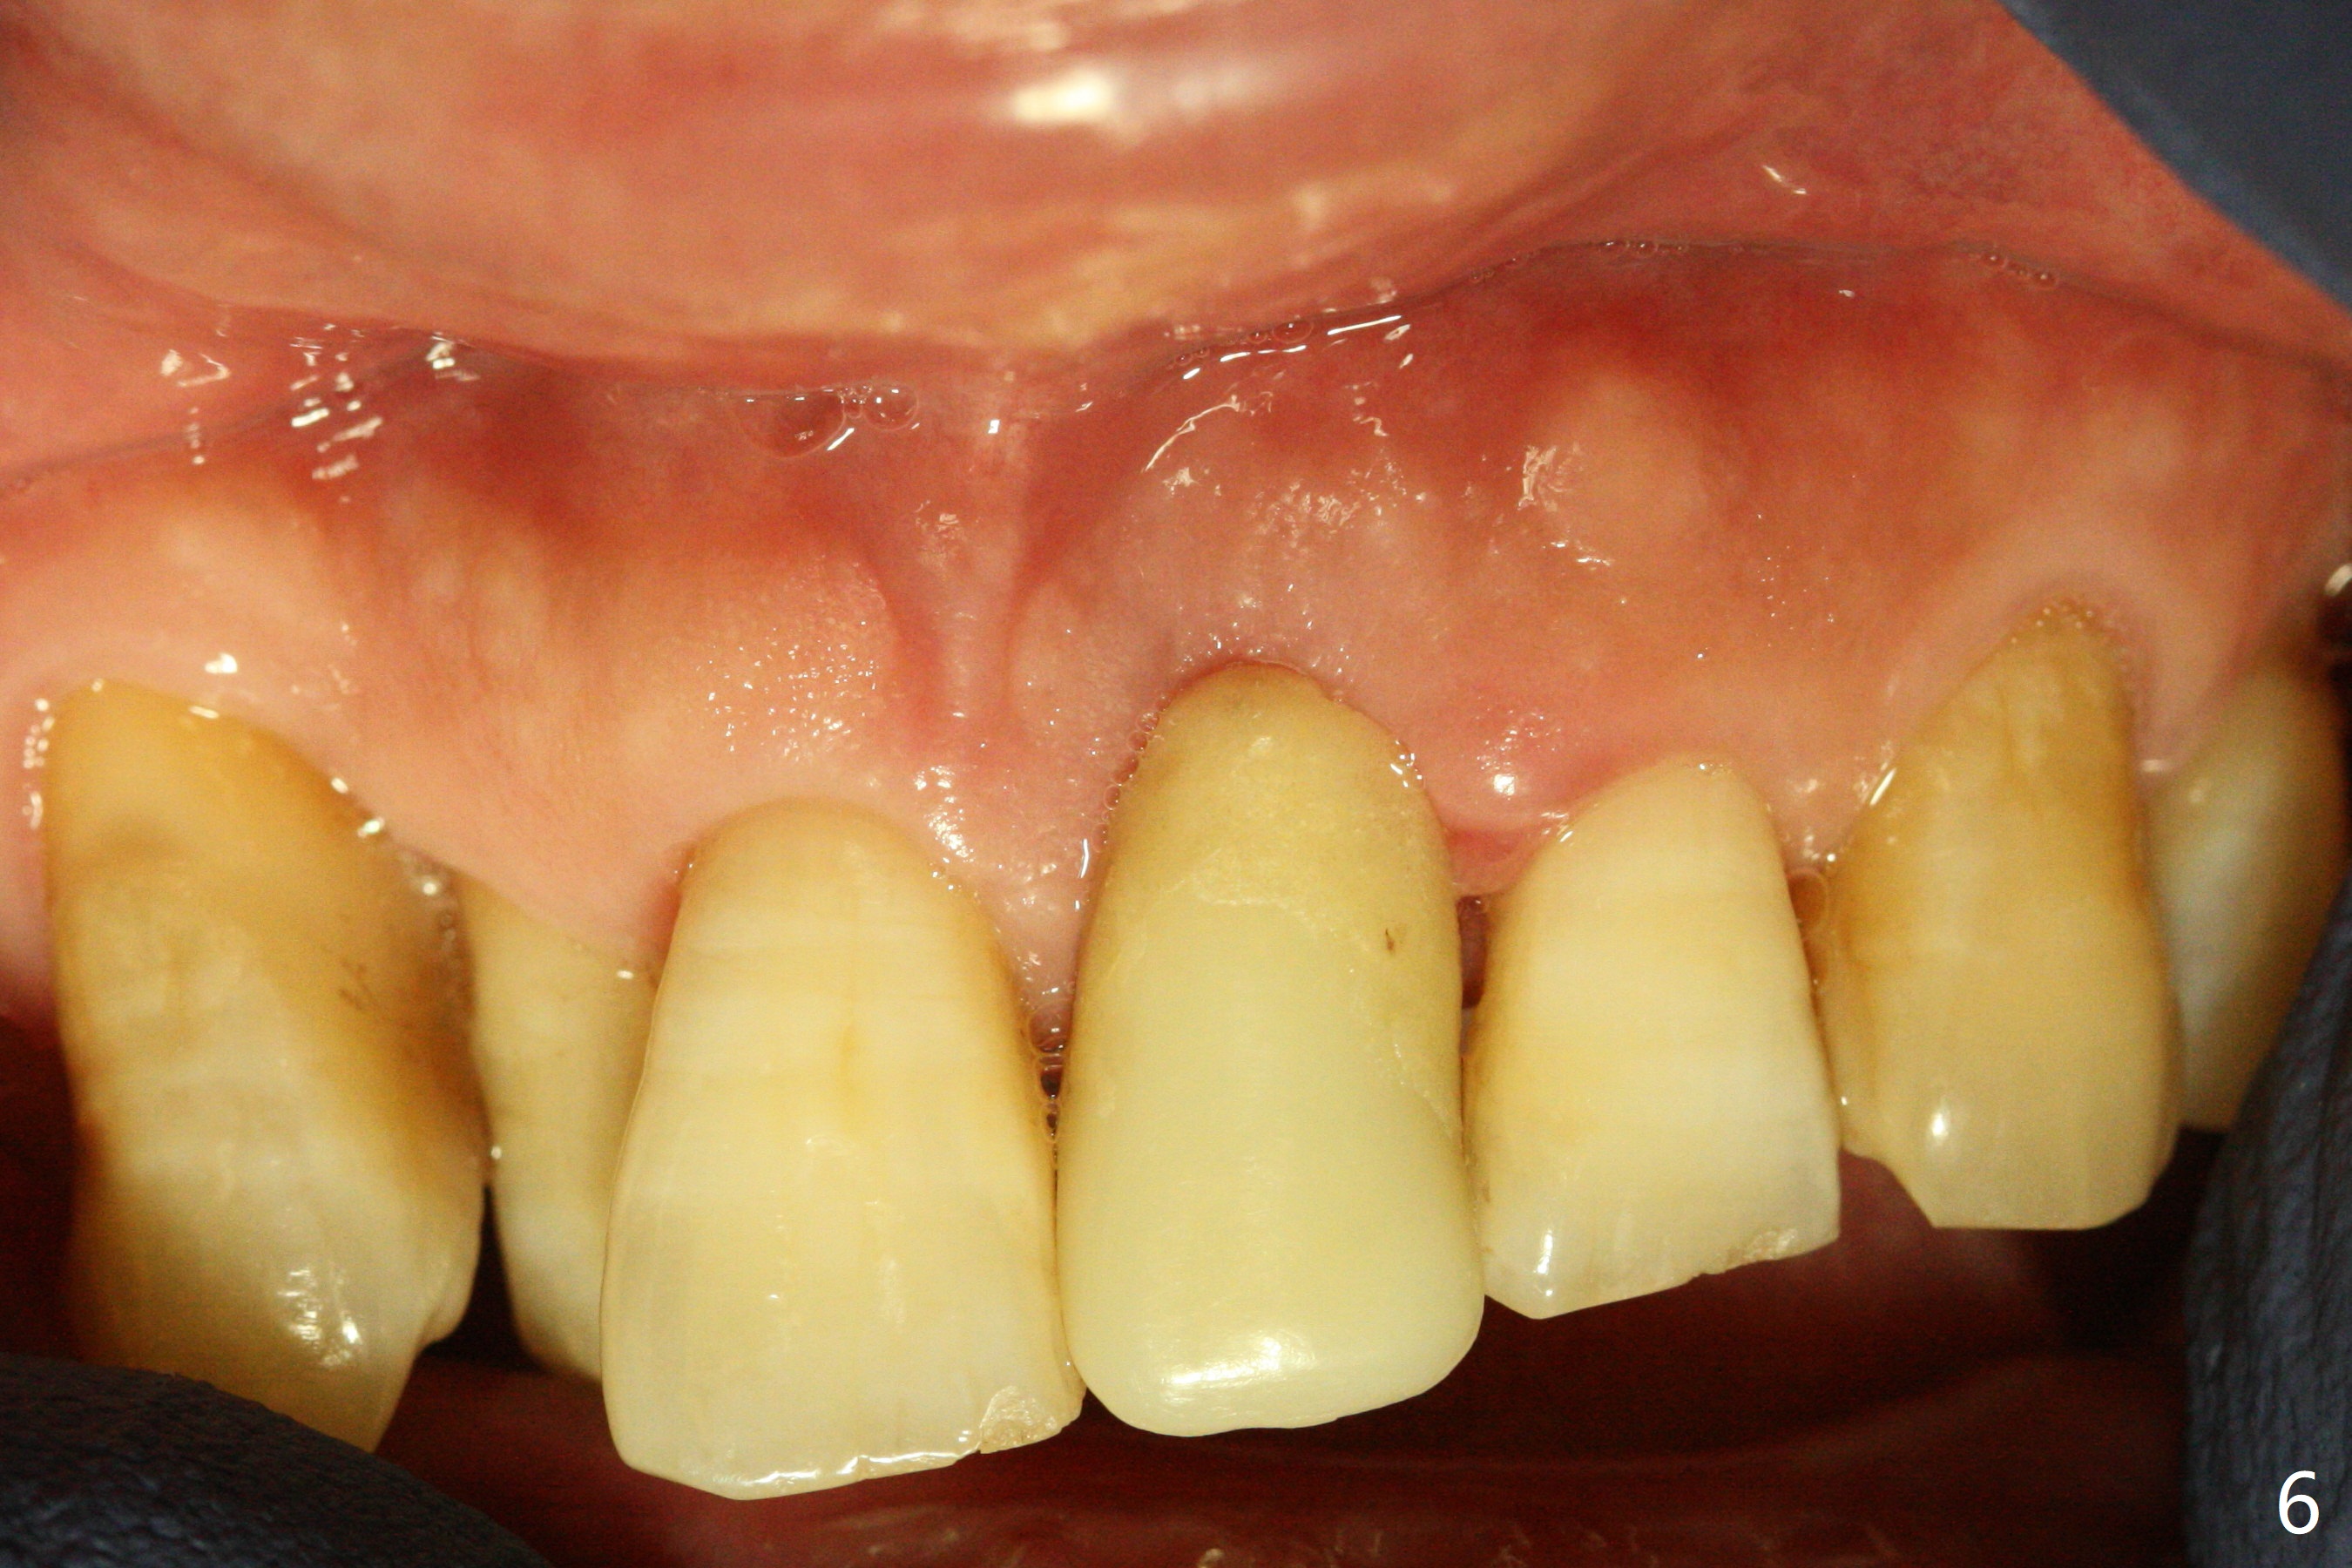

Immediately preop PA confirms loss of the buccal plate at #9 (Fig.1 *). In contrast the palatal crest is ~ 4 mm subgingival (WNL) after extraction. When initial osteotomy reaches 18 mm, there is moderate hemorrhage, probably due to close to the nasal floor (Fig.2 red dashed line). Following sequential osteotomy, a 3.8x15 mm dummy implant is placed partially (Fig.3 (pink: apical osteotomy)). After placement of an implant with the same dimension as the dummy's (Fig.4), PRF is laid against the inner surface of the buccal defect and allograft (Fig.5 *) is packed mainly in the buccal gap before and after insertion of a 4.5x5(4) mm abutment. The patient is satisfied with the immediate provisional (Fig.6: 1 week postop). The buccal margin of the provisional is shortened with exposure of bone graft to facilitate gingival downgrowth (Fig.6: 1 month postop). The buccal plate seems to collapse nearly 2 months postop (Fig.8 *), probably due to loss of the bone graft. The abutment is exposed buccally (Fig.9). The margin of the abutment is reprep and the provisional is relined so that the margin of the provisional is palatal to the buccal gingival margin. In 2-3 weeks, a temporary abutment will be used to bulk the buccal gingiva. The gingiva seems to have downgrown; the buccal plate collapse appears normal nearly 3 months postop (Fig.10). The patient is more concerned about cross bite at #7. A temporary abutment is not used. The bone graft remains in place 3.5 and 4.5 months postop (Fig.11,12 *). Between 3 and 4 months postop, the mesial surface of the abutment has been trimmed (Fig.12 >). Since the mesial surface of the tooth #10 will be reduced (white curved line) to correct the upper dental midline, an angled abutment (red line) seems to be necessary to shift the provisional distal.